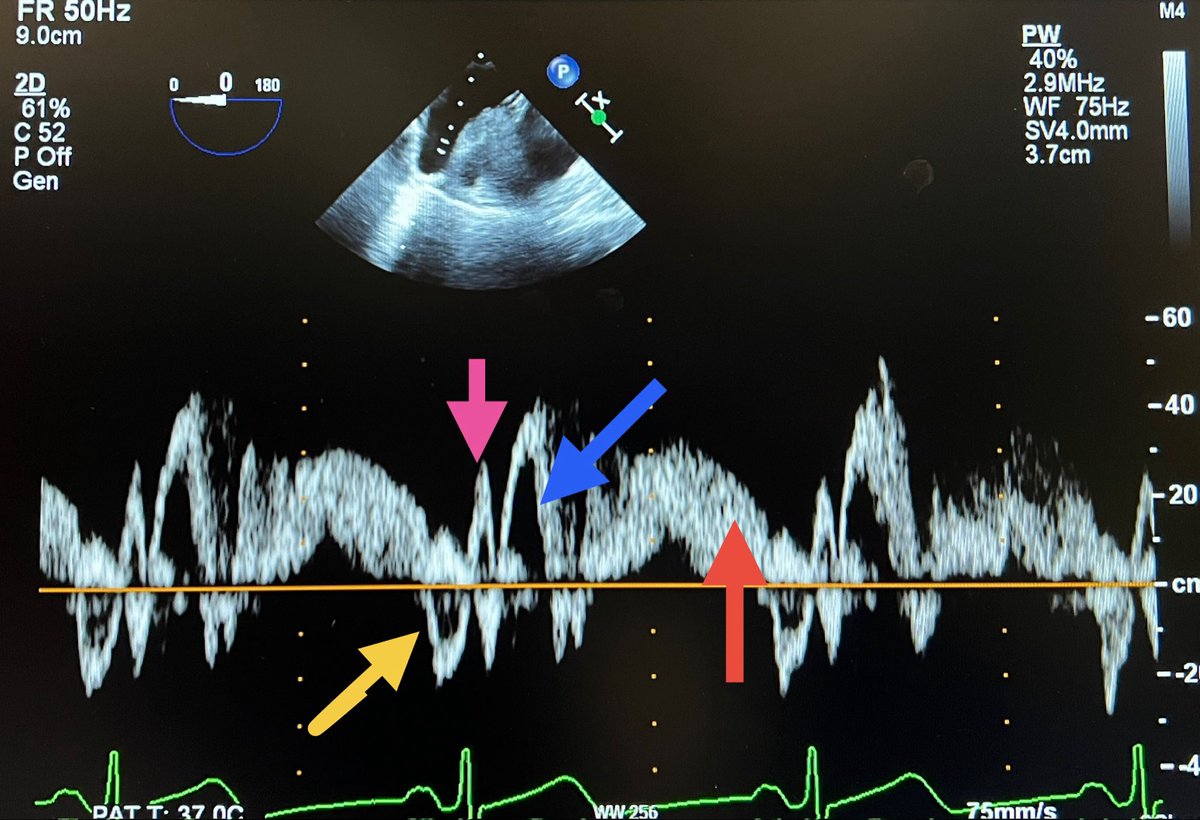

#echofirst ✅ Time to close out. See answer below. ✅ Pink: S1 (due to atrial relaxation), Blue: S2 (systolic), Orange: diastolic, Yellow: atrial reversal ✅ Prominent Ar, slow diastolic velocity decline & systolic predominance indicate DD & ⬆️ LVEFP ✅ Most got it right! 🙏

#echofirst ✅ Simple Doppler quiz for trainees ✅ Identify the waves on this tracing & the diagnosis @BryanTanMD @Hragy @JaeKOh2 @EchoSoliman @argulian @iamritu @bwoody58 @PWesslyMD @PWengrofskyMD @DavidWienerMD @JohnHenryDean